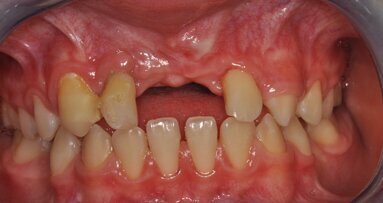

W fazie planowania leczenia wykonano badania OPG oraz CBCT. Badania uwidoczniły masywny zanik części zębodołowej wyrostka żuchwy do jej trzonu – klasa 3. Zanik ten nie wykluczał leczenia pacjentki, jednak eliminował żuchwę jako miejsce dawcze dla ewentualnych przeszczepów kości dla rehabilitacji szczeki. W szczęce uwidoczniono masywny zanik części zębodołowej wyrostka w odcinku przednim wraz ze zwiększeniem upowietrznienia zatok szczękowych i deformacją płaszczyzny powierzchni kości. Jest to obraz typowy dla pacjentów użytkujących przez lata protezy całkowite w szczęce przy współistniejącym uzębieniu resztkowym w odcinku międzybródkowym żuchwy. Taki stan nazywamy zespołem Kellego (Ryc. 1).

Taki stan jest ogromnym utrudnieniem dla leczenia protetycznego bezzębnej szczeki przez niekorzystną relację płaszczyzny pola podparcia protezy do płaszczyzny protetycznej. Znaczny stopień zaniku wyrostka w okolicy podnosowej eliminuje to miejsce z zabiegów GBR. Do rozważań pozostają zatem odcinki boczne w rzucie zatok szczękowych. W przypadku opisywanej pacjentki CBCT uwidoczniło zadowalający wymiar wertykalny przy ubytku horyzontalnym w postaci bagnetowatego szczytu wyrostka zębodołowego (Ryc. 2).